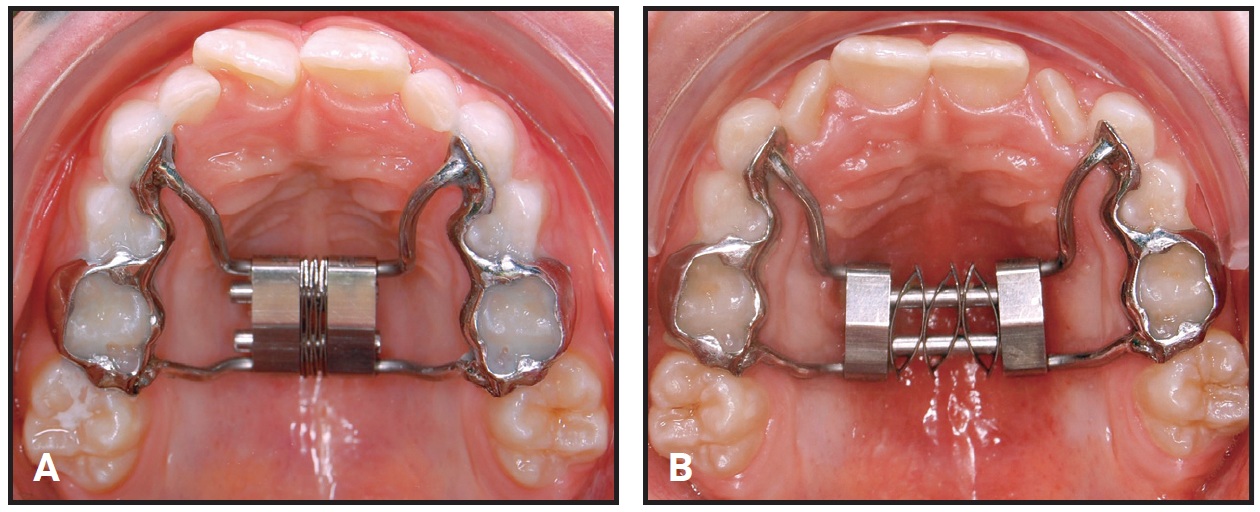

Fig. 4 Case 1. A. Self Expander in place at beginning of treatment. B. After six months of expansion.